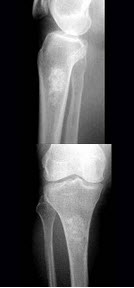

215、单项选择题

男,46岁,双髋部疼痛,实验室检查血钙升高,尿本周蛋白(+),结合图像,最可能的诊断是()

A.骨髓瘤

B.骨质疏松症

C.骨转移瘤

D.骨囊肿

E.动脉瘤样骨囊肿